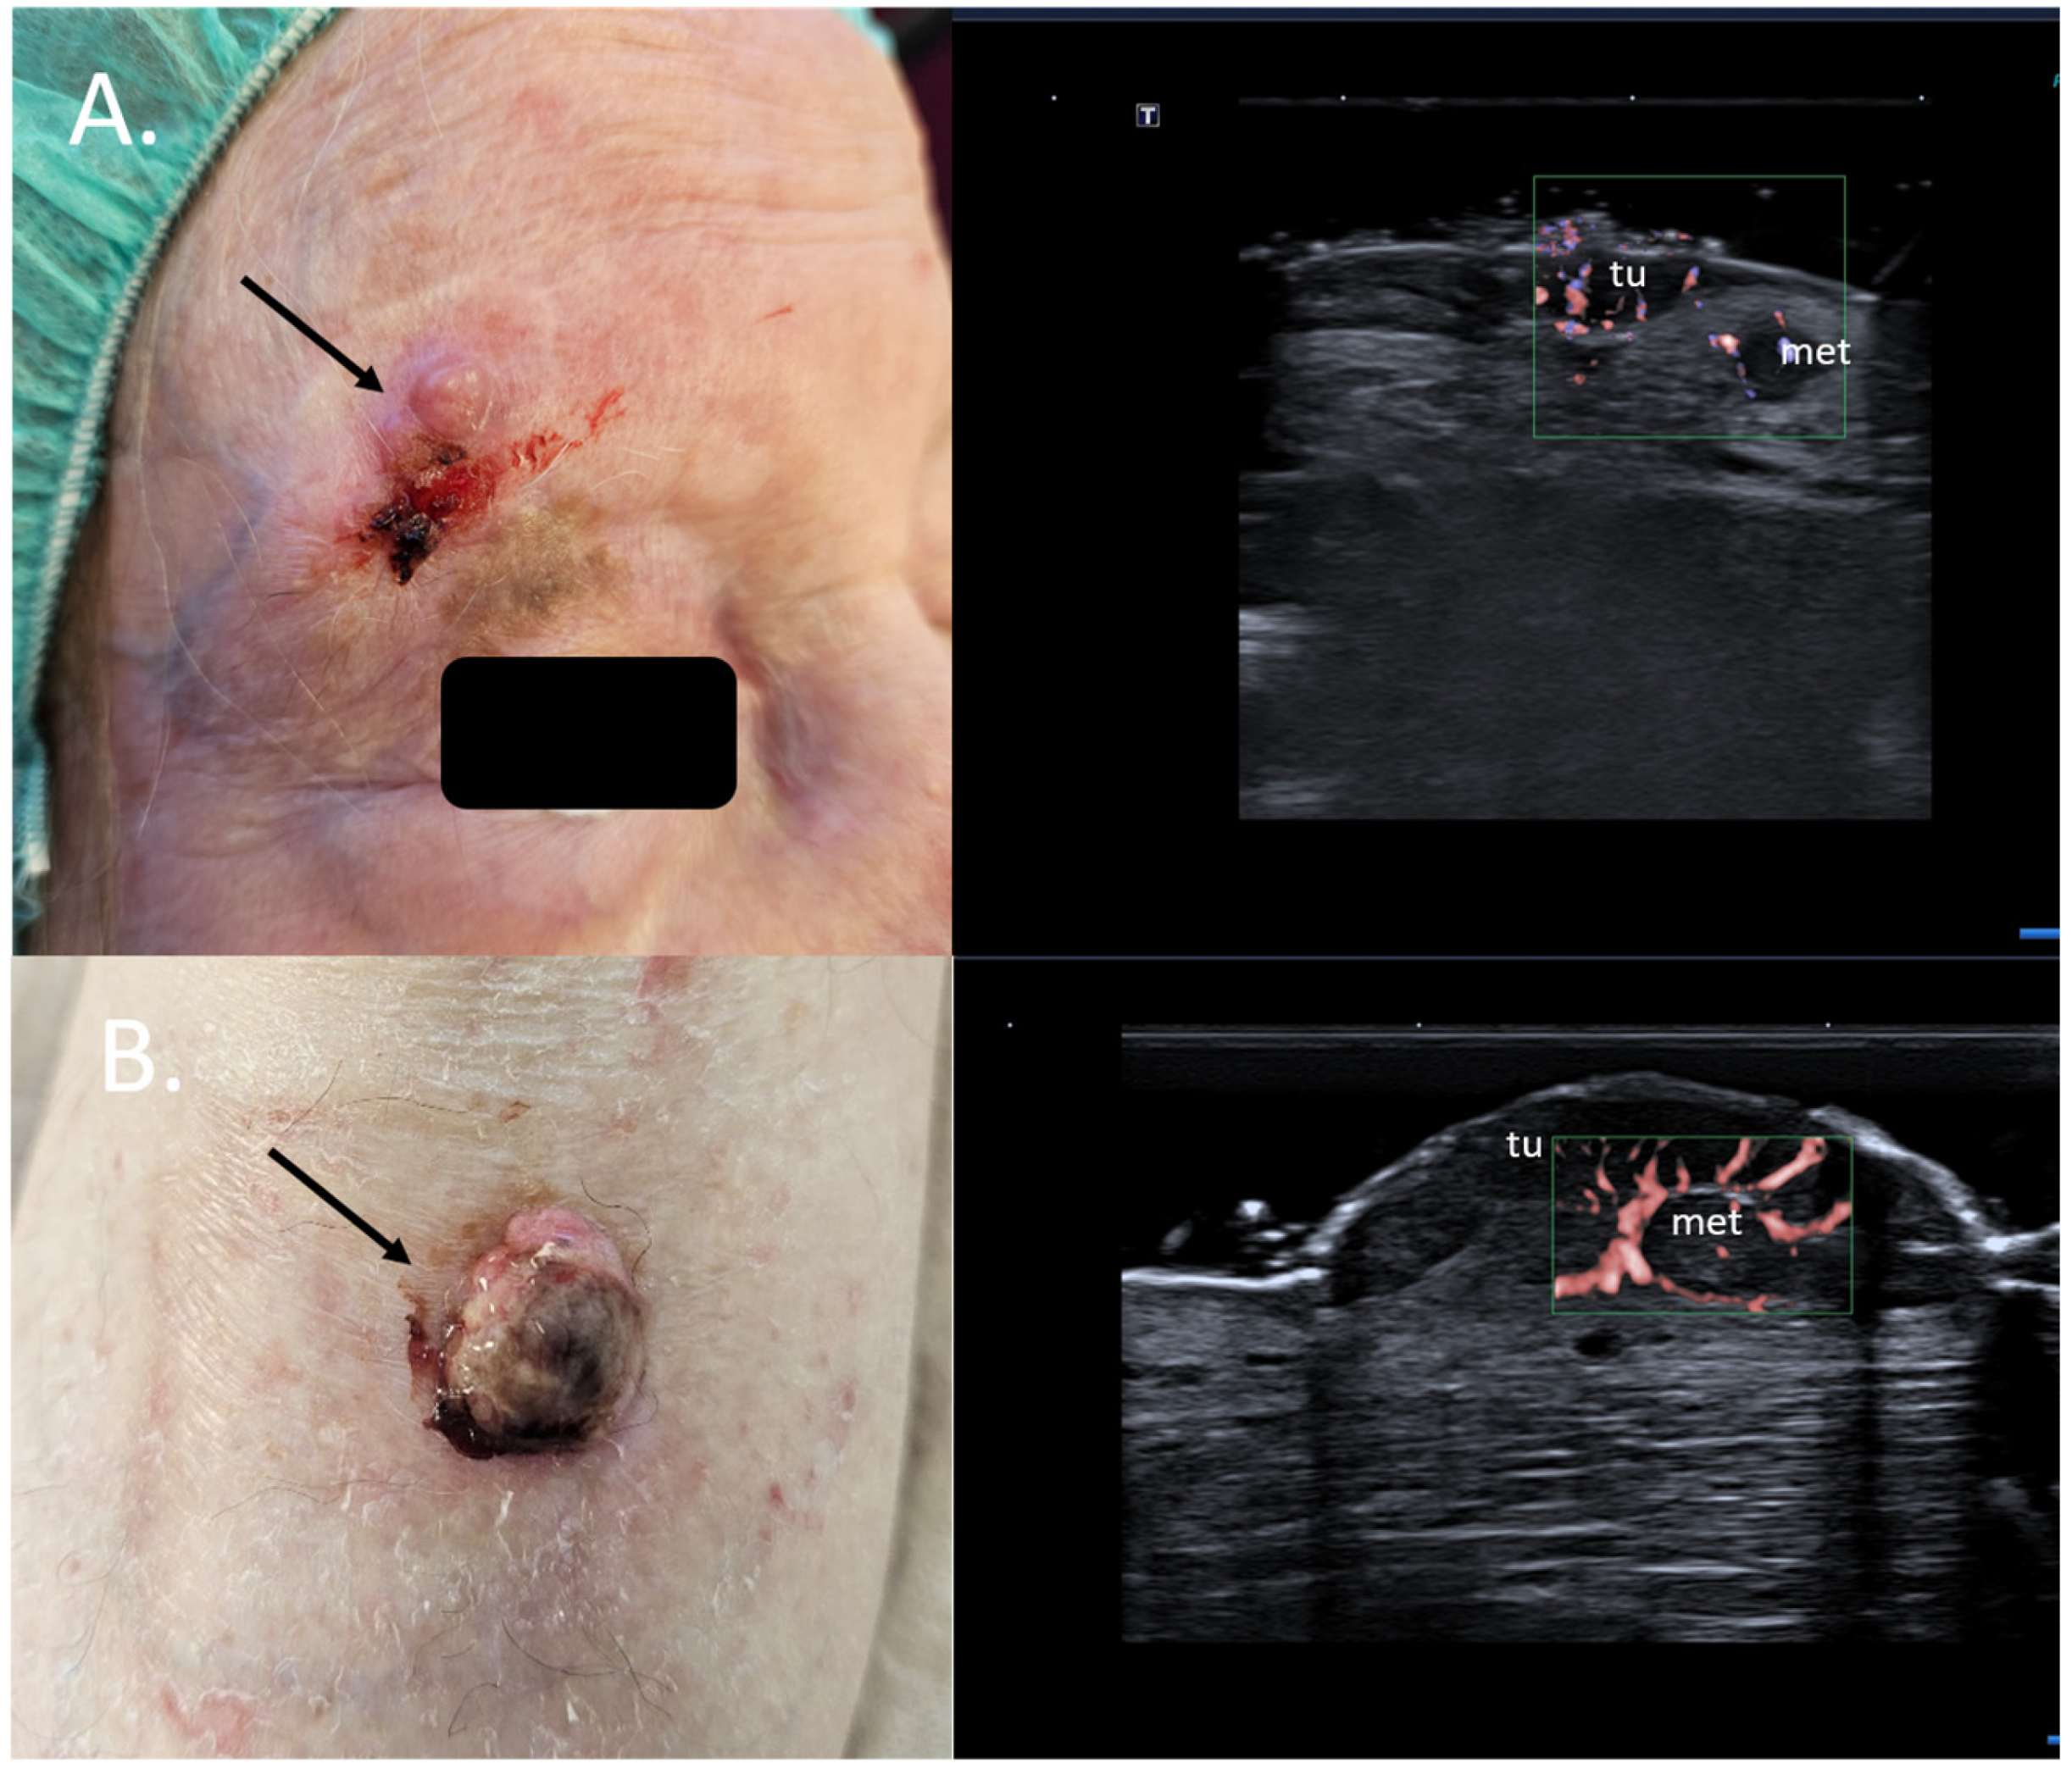

11. Intraoperative Guidance

7. Choice of Surgical Approach